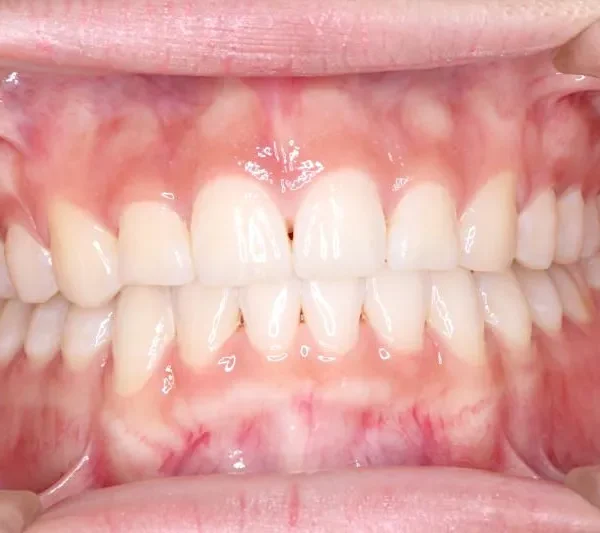

初診時

初診時年齢 小学校6年生 (女性) 主訴 犬歯がずれている・噛み合わない

診断名 叢生・交叉咬合 装置名

右下の犬歯がずれて生え噛み合わせの邪魔をしています。

歯は抜かず、上下マルチブラケット装置を使用し治療いたしました。

治療回数54回、9年3ヶ月の治療期間で矯正治療を終了しました。

噛み合わせのずれは、ぱっと見綺麗に見えますが、放っておくとのちのち噛みにくくなり、顎関節にまで影響を及ぼしかねません。